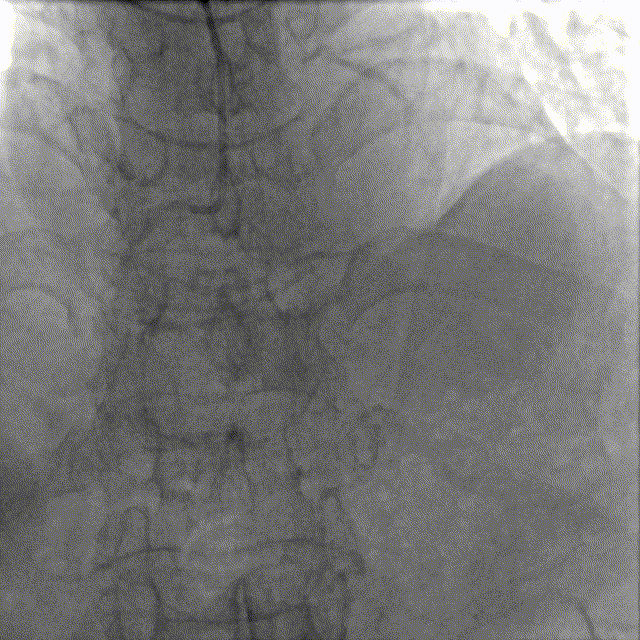

造影如下

患者左主干前三叉1,0,1型病变,主干末端偏心40%狭窄;前降支病变自开口延续至中段,口部80%狭窄,中段80%狭窄,病变位置钙化严重;回旋支近段约30%轻度狭窄,第一及第二钝缘支开口80%局限病变。